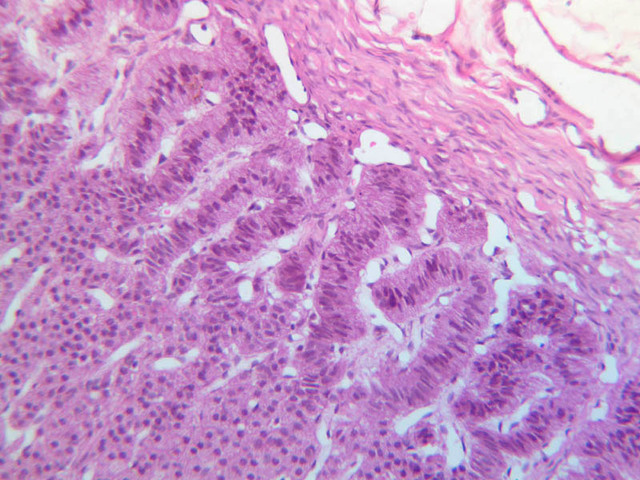

Examine slide B-56 (H&E [2.5x, 10x, 20x, 40x-labeled] [10x, 20x, 40x-labeled] [20x, 40x] [10x, 20x, 40x-labeled] [10x, 20x, 40x]). The connective tissue capsule of each parathyroid gland is continuous with that of the thyroid gland. It extends into the substance of the gland, dividing it into poorly defined lobules. Fat cells may separate the groups of cells and increase with age. Note the rich capillary network. The parenchyma is composed of two types of cells: (1) Principal or chief cells and (2) oxyphil cells. The polygonal chief cell is by far the more numerous cell type. Its nucleus is centrally located and has a vesicular chromatin pattern with a prominent nucleolus and its cytoplasm stains rather lightly. Oxyphil cells, which are less regular in shape and considerably larger than chief cells, are scattered singly or in small clusters. Their nuclei are smaller and more condensed than those of the chief cells and, owing to a very rich complement of mitochondria, their cytoplasm is distinctly acidophilic.